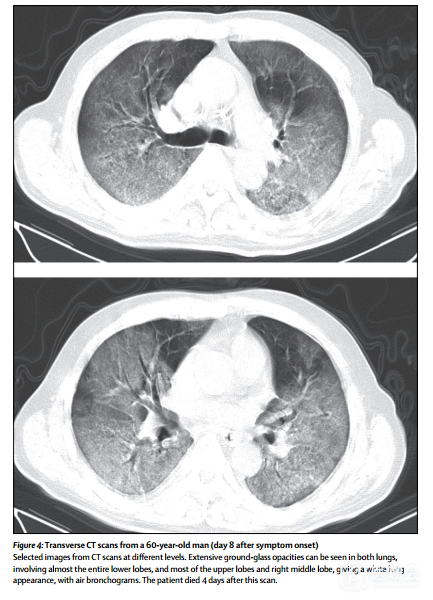

入院后第12天死亡的患者是一名60岁(患者1)合并慢性肺部疾病(结核病)的患者。症状发作后第8天的CT扫描显示,两个肺部都有广泛的毛玻璃样混浊,呈现为白色肺部外观(图4)。

图4 患者1症状发作8天后的横向CT扫描影像